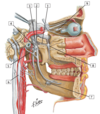

#1

#1 - superficia temporal artery

32

#2

#2 - occipital artery

33

#3

#3 - internal carotid artery

34

#4

#4 - external carotid artery

35

#5

#5 - common carotid artery

36

#6

#6 - superior thyroid artery & superior laryngeal branch

37

#7

#7 - ascending pharyngeal artery

38

#8

#8 - lingual artery

39

#9

#9 - facial artery

40

#10

#10 - posterior auricular artery

41

#11

#11 - maxillary artery

42

#1

#1 - middle meningeal artery

43

#2

#2 - buccal artery

44

#3

#3 - external carotid artery

45

#4

#4 - superior thyroid artery

46

#5

#5 - common carotid artery

47

#6

#6 - internal carotid artery

48

#7

#7 - facial artery

49

#8

#8 - maxillary artery

49

#9

#9 - superficial temporal artery

50

#1

#1 - pterygoid plexus

51

#2

#2 - superior laryngeal vein

52

#3

#3 - middle thyroid vein

53

#4

#4 - inferior thyroid veins

54

#5

#5 - subclavian vein

55

#6

#6 - internal jugular vein

56

#7

#7 - common trunk for facial, retromandibular, and lingual veins

57

#8

#8 - external jugular vein (cut)

58

#9

#9 - retromandibular vein

58

#10

#10 - superficial temporal vein and artery